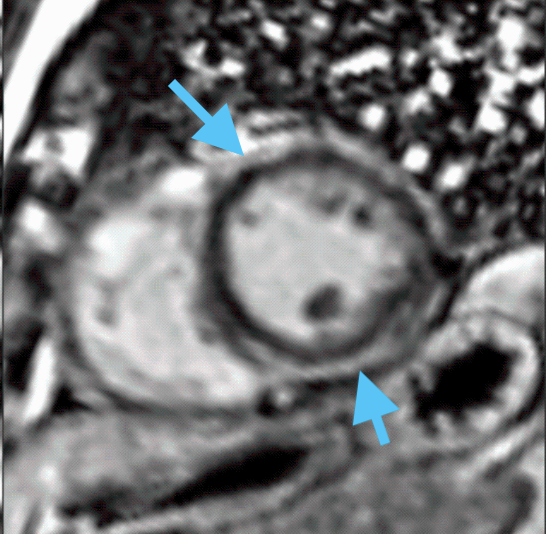

Figure 3: Representative CMR with patchy subendocardial LGE from cohort with variants of uncertain significance.